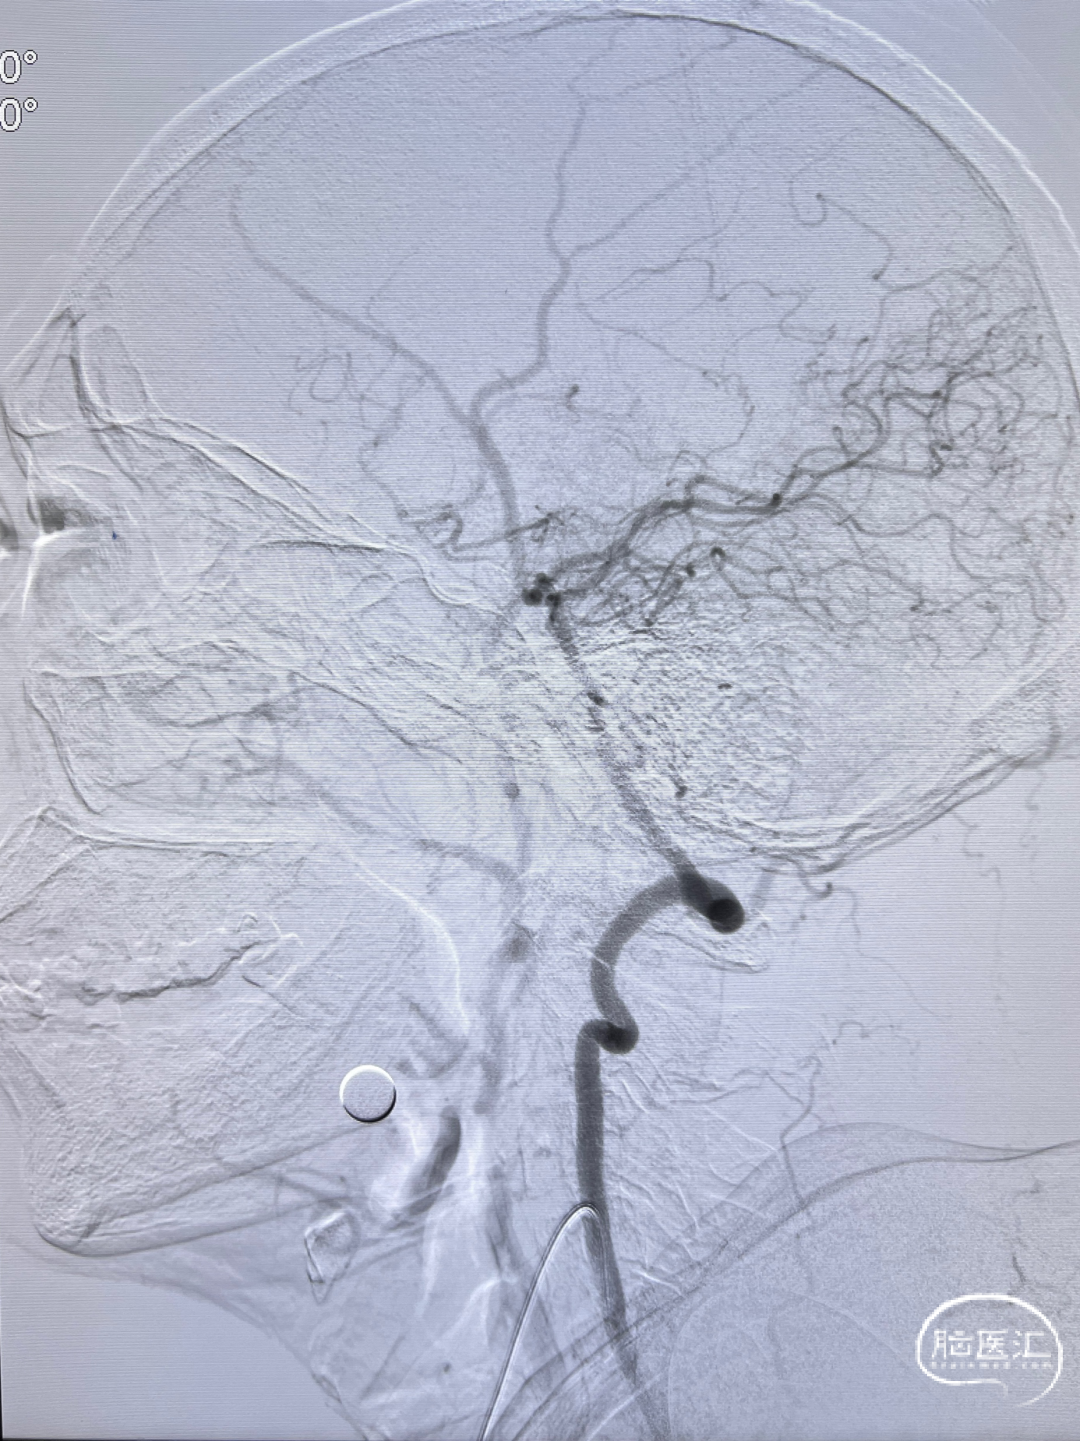

左侧颈内动脉正侧位造影,狭窄解除。